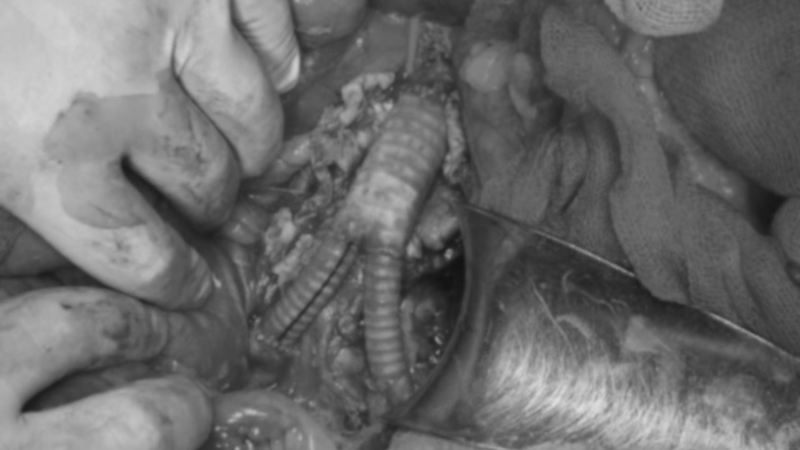

Khi mở bụng, kíp mổ phát hiện điểm vỡ khoảng 0,5 cm ở thành sau động mạch chủ bụng, máu tụ lan rộng trong khoang sau phúc mạc. Các bác sĩ tiến hành khống chế động mạch chủ và động mạch chậu, kiểm soát chảy máu, sau đó thay đoạn mạch tổn thương bằng mảnh ghép nhân tạo chữ Y để tái lập lưu thông dòng máu.